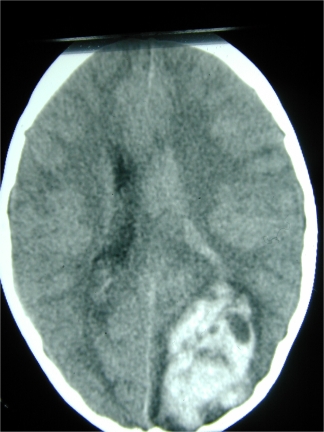

For example bleeding at the back of the brain on one side in this 8 year-old girl caused loss of the field of vision on the opposite side, in both eyes. This is called homonymous hemianopia.